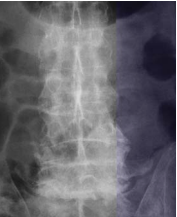

Mr O, an elderly man, was recently admitted for severe low back pain of two months duration. He had chronic low back pain on and off for many years. His pain this time was so severe that he could sit for only a short while. He could barely walk a few meters. The neurological examination was normal. X-ray of his lumbar spine revealed the feature of “’ bamboo spine’ typical of ankylosing spondylosis. There was a fracture through the ossified L5-S1 disc space which was widely opened. Flexion and extension x-ray showed there was considerable instability at the L5-S1 segment. Mr O underwent a two-stage surgery. The 1st stage was posterior L4 to S1 pedicle screw instrumentation. The 2nd stage anterior L5-S1 strut grafting with titanium mesh and fibular allografts was performed 5 days later. Post surgery, Mr O was relieved of his pain and was ambulating.

Pathology of Ankylosing Spondylitis The basic pathology of ankylosing spondylitis is inflammation followed by ossification of ligaments surrounding the spinal column. The process usually begins in the sacroiliac joint causing sacroiliitis which shows on x-ray as fizziness of sacroiliac joint. The process extends up the spine to a variable extent. At times the whole spine may be involved resulting in a completely rigid spine. The ossification of the spinal ligaments results in bone bridges across the adjacent vertebrae giving rise to the classical description of bamboo spine noted in the spinal x-ray. The ligaments surrounding the hip joints may also become ossified, resulting in stiff hips. When this occurs, patient becomes severely disabled because he will not even able to sit upright.